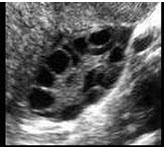

26、单项选择题

女,27岁,下腹部疼痛数月,体检:右侧附件区增厚、增大,B超检查如图所示,最可能的诊断为()

A.右侧卵巢囊肿

B.右侧输尿管扩张

C.右侧输卵管积液

D.盆腔积液

E.以上都不是